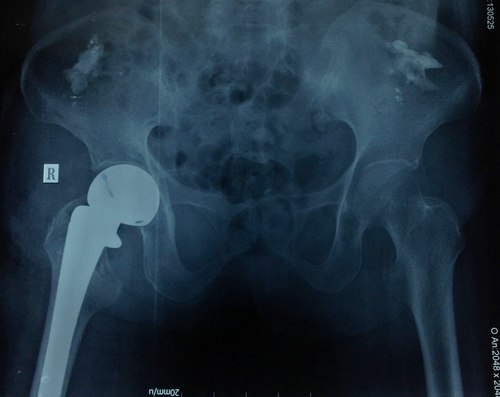

Hình ảnh phim chụp khớp háng bệnh nhân 93 tuổi. Ảnh: T. Đ.P

Bác sĩ Phú cho biết, bệnh nhân được nhanh chóng phẫu thuật thay khớp háng chuôi dài thế hệ mới. Đây là loại khớp háng mới được ứng dụng cho các loại gãy cổ xương đùi phức tạp có đường gãy lan xuống dưới làm mất vững. Sau hậu phẫu 7 ngày, bệnh nhân đã vận động nhẹ tại giường chân phải và bớt đau đớn. Khả năng sau 3 ngày nữa là bệnh nhân có thể xuất viện.